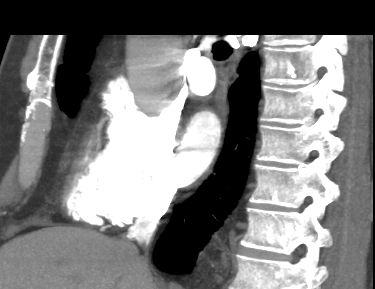

Компьютерная томография сердца является высокотехнологичным лучевым методом исследования, который позволяет оценить строение и особенности анатомии камер сердца, визуализировать состояние перикарда, коронарных артерий и восходящей части и дуги аорты.

В нашей клинике КТ сердца проводится на новейшем 128-срезовом мультиспиральном компьютерном томографе экспертного уровня TOSHIBA AQUILION CXL. Томограф послойно сканирует анатомическую область сердца, производя срезы толщиной от 0,5 мм. Методика сканирования сердца 128-срезовым КТ сканером производится с использованием перспективной синхронизации по электрокардиографии (ЭКГ).

Протокол сканирования предусматривает внутривенное болюсное контрастирование. Контрастное вещество на основе йода вводится пациенту внутривенно непосредственно во время исследования. Контраст равномерно распределяется по сосудистой системе, благодаря чему становится хорошо видна восходящая часть аорты с отходящими от нее венечными артериями и дуга аорты. По результатам обследования можно решить, нуждается пациент в проведении стентирования коронарных артерий или нет.